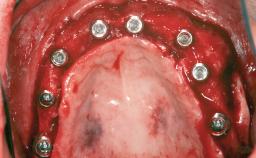

Ridge Preservation and Implant Placement for a Fixed Dental Prosthesis After a Car Accident

It is well known to clinicians that any removal of teeth will, over time, cause the dimensions of the alveolar ridge to be reduced by resorption of the bundle bone and by changes related to external modeling. This development is particularly evident in the crestal region with its thin buccal bone that consists of bundle bone almost entirely. The facial bone will rapidly resorb as blood supply from the periodontal ligament gets disrupted (Araújo and Lindhe 2005). There is no reason why traumatic tooth loss should not have the same consequences. It takes more than achieving implant osseointegration for a treatment outcome to be considered successful. No deficiency of bone or soft tissue is acceptable when an ideal esthetic outcome is the goal. Several articles (Sanz and coworkers 2011; Vignoletti and coworkers 2011) have reported on techniques of improving the alveolar ridge for implant treatment, notably focusing on protecting tissues from resorption.

Case Type Extended Space

Jaw Maxilla

Area Anterior|Posterior

# of Teeth 6

# of Implants 4

Type of Implants One-Piece|Reduced-Diameter

Bone Augmentation Horizontal|Simultaneous|Sinus Floor Elevation|Staged

Augmentation Materials Xenogenous|Membrane